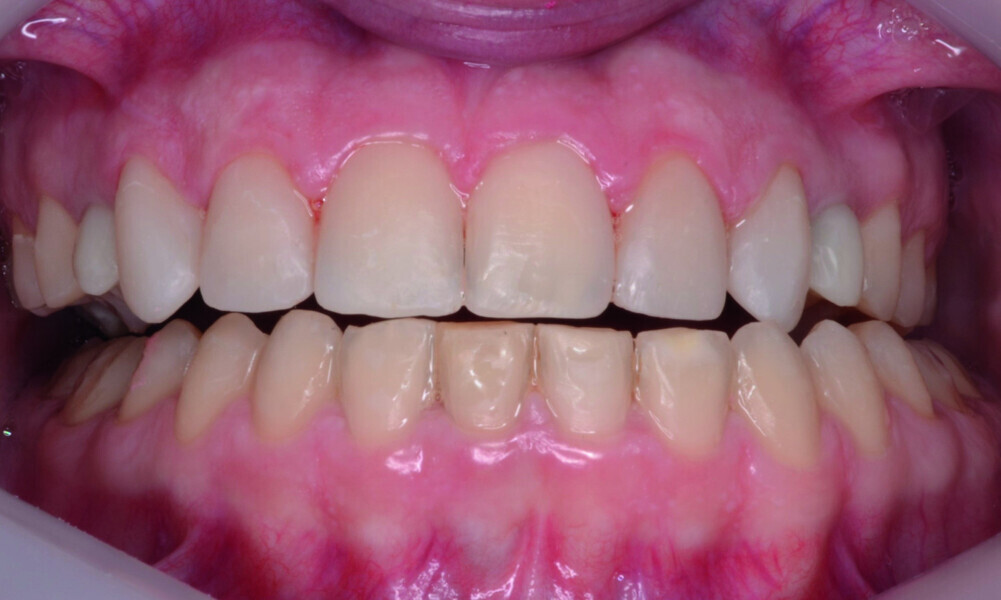

Orthodontic management of maxillary lateral incisors agenesis